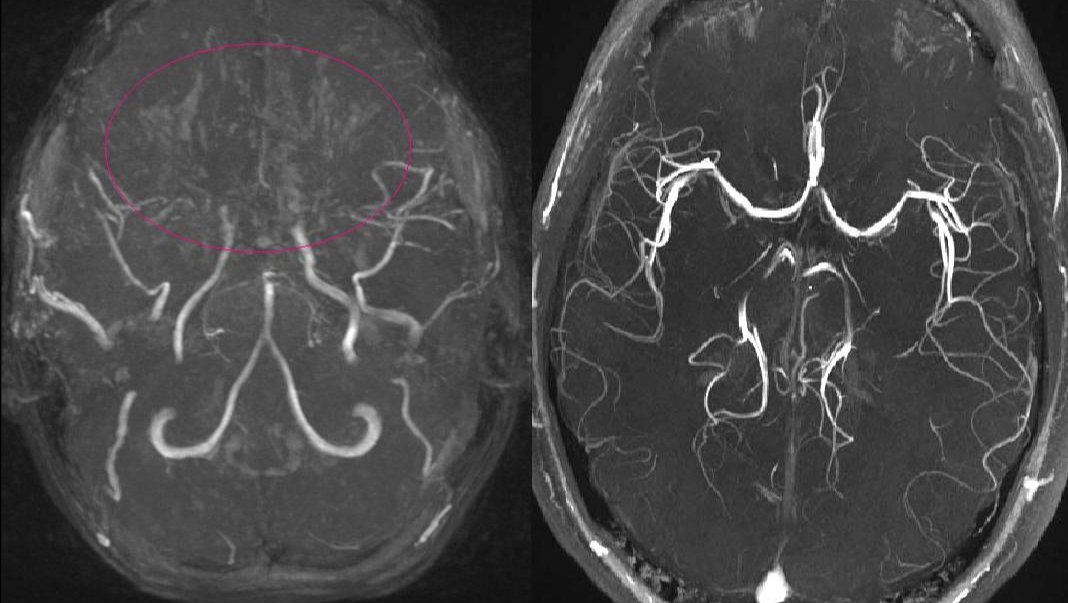

Manyetik Rezonans Anjiyografi (MRA), serebral anjiyografinin alternatifi olarak kullanılabilir. Bu yöntem, manyetik rezonans görüntüleme (MRG) prensiplerini kullanarak damarların görüntülerini oluşturur. Genellikle serebral anjiyografiye göre daha düşük risk içerir.[7]

Tanıda etkili olan bir diğer unsur, hastanın klinik belirtileri ve görüntüleme bulgularıdır. Moyamoya hastalığının belirgin bulguları genellikle supraclinoid iç karotis arterleri ve bunların proksimal dallarını içerir.[7]

Moyamoya hastalığının teşhisinde serebral anjiyografi genellikle en güvenilir yöntem olmakla birlikte, MRA gibi non-invaziv yöntemler de kullanılabilir. Teşhis sürecinde hastanın genel sağlık durumu, alerji öyküsü ve kontrast madde kullanımına karşı hassasiyet dikkate alınmalıdır. Teşhis, uzman bir sağlık profesyoneli tarafından detaylı bir değerlendirme sonucunda konmalıdır.[7]